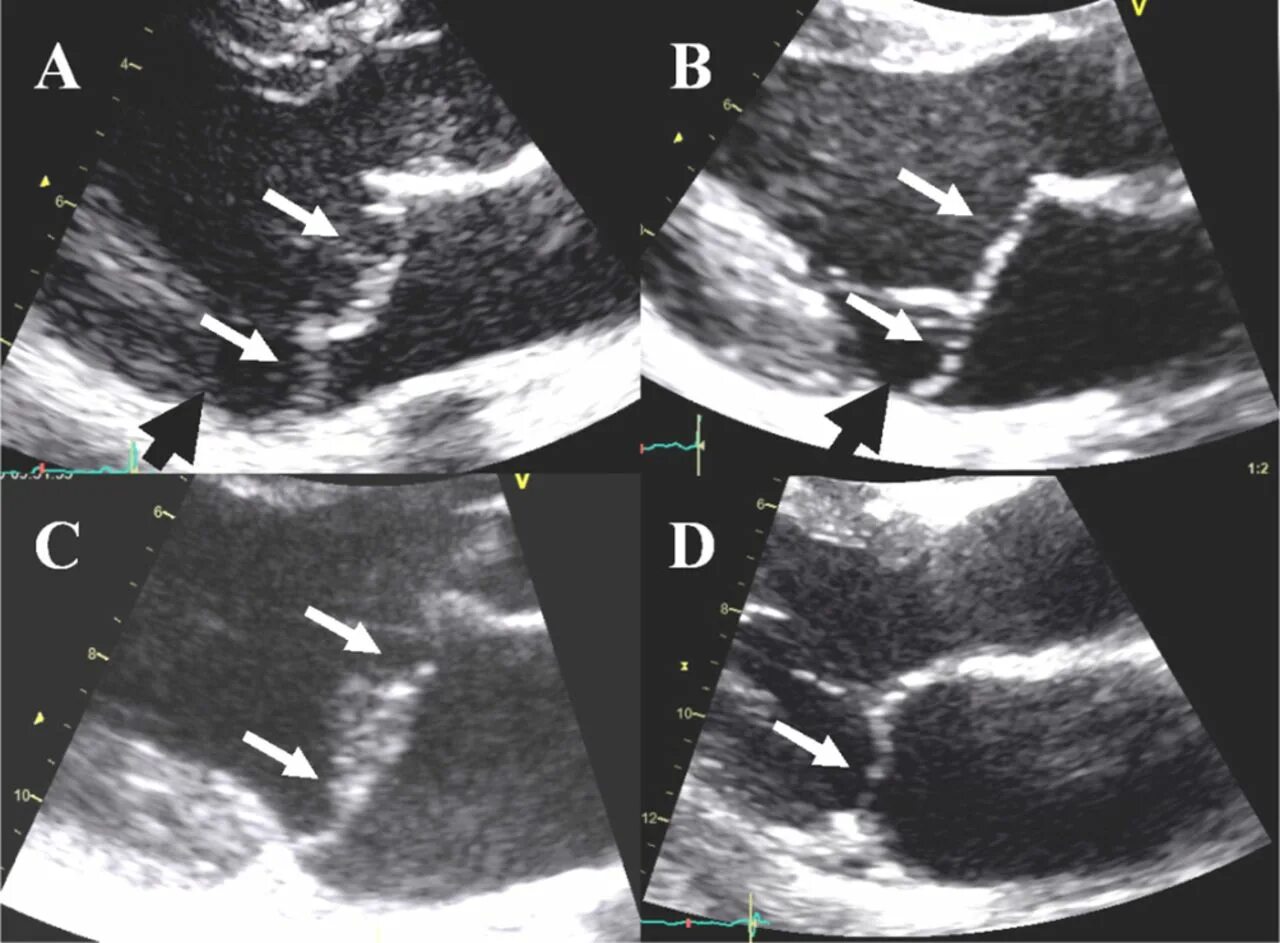

Аневризма мпп без